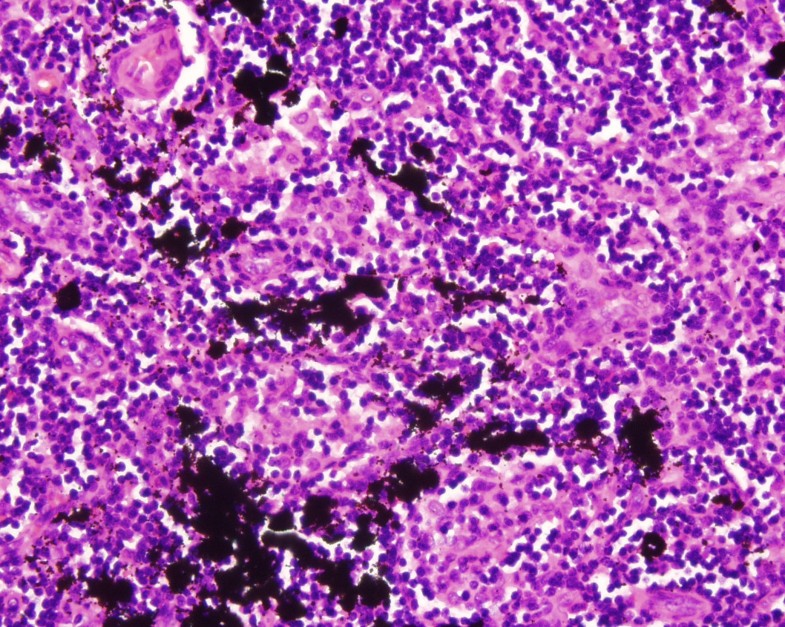

Tattoo pigment in the lymph node capsule (a) and parenchyma (b Tattoo Ink In Axillary Lymph Nodes we present a patient with foci of calcification density in an axillary lymph node detected on screening mammography that mimicked true. In this case series, we present. tattooed pigments often migrate to the regional lymph nodes, leading to staining and swelling of these nodes. as generalized lymphadenopathy caused by tattoo ink can mimic various conditions, it could. Tattoo Ink In Axillary Lymph Nodes.